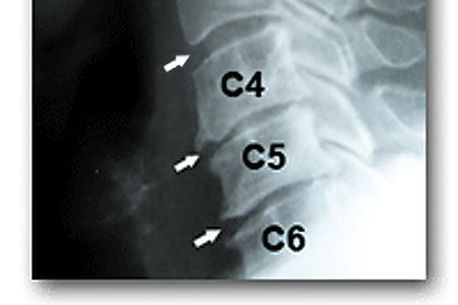

fiind diagnosticat cu fractură de coloană cervicală la nivelul C4,

bipareză brahială (n.r. – la membrele superioare) și paraplegie

(n.r. – o pareză a membrelor inferioare).

producându-se cu un nivel cervical mai sus. „A fost o secțiune

totală de măduvă datorată unei luxații totale a C4 (n.r. – vertebra

nr. 4 cervicală). Acum s-au realiniat vertebrele, se află pe

ventilație asistată și un pronostic poate fi dat abia după 72 de

ore. Dacă va reuși să respire singur, va fi un punct favorabil

pentru el”, a explicat, imediat după operație, Octavian Cîmpian,